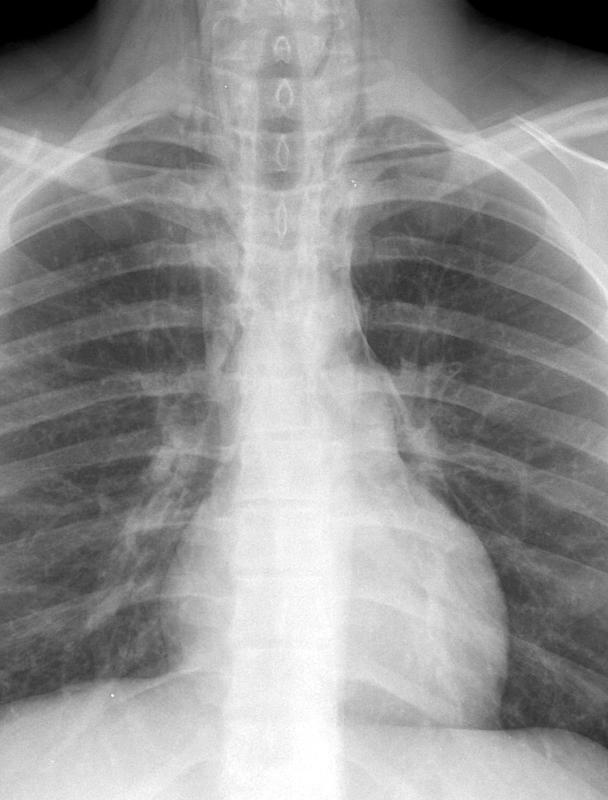

Pneumomediastinum 2